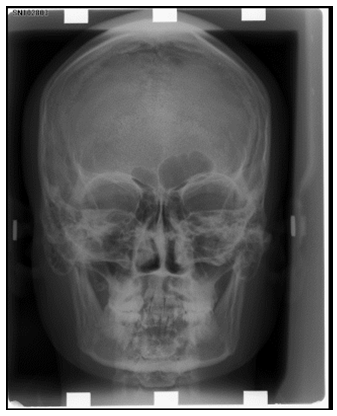

Number of bones that from the orbit:

List the bones that from the orbit and what part of the orbit

Roof: Frontal

Floor: maxillary and zygomatic

Medial Wall: lacrimal, ethmoid

Lateral wall: Zygomatic, Sphenoid

Extra: Palatine bone

List the paranasal sinuses: